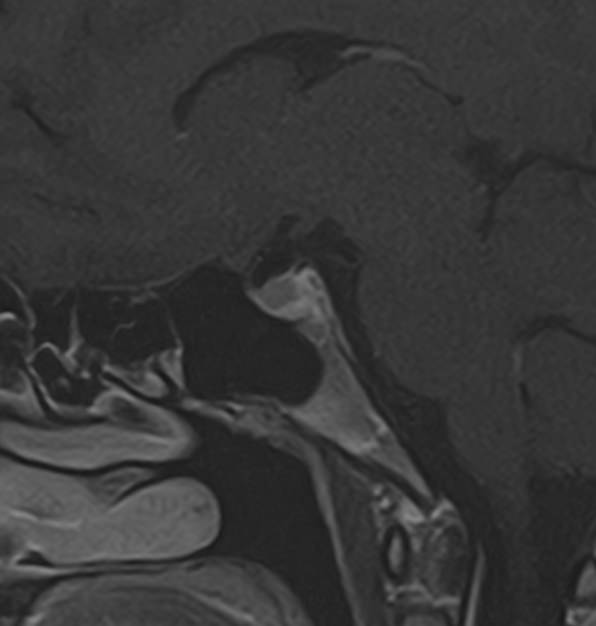

Для выявления опухолевых образований гипофиза проводится МРТ гипофиза с контрастным усилением. Для этого пациенту внутривенно вводится препарат, содержащий контрастное вещество, имеющее в своем составе металл гадолиний. Контрастное вещество избирательно накапливается в патологических очагах, интенсивность этого накопления можно оценить визуально, а также с помощью компьютерной программы — в цифровом выражении.

Метод позволяет создавать детализированные изображения области турецкого седла и является лучшим способом диагностики любых объемных образований гипофиза. С помощью МРТ гипофиза можно выявить макроаденомы и большинство микроаденом гипофиза размером от 1 мм.

В клинике «Доступная медицина» проводится МРТ гипофиза с контрастом на современном высокопольном томографе TOSHIBA VANTAGE TITAN 1,5 Тесла. Индукция магнитного поля 1,5 Тесла обеспечивает высокую четкость изображения и отвечает мировым стандартам качества диагностики заболеваний центральной нервной системы.